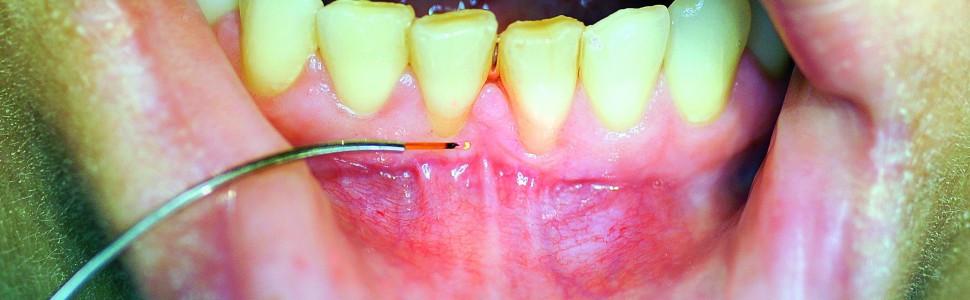

W pracy omówiono zasady cięcia tkanek laserem diodowym w jamie ustnej, pozwalające na zmniejszenie ryzyka urazu termicznego otaczających struktur. Dobór techniki cięcia i prawidłowe ustawienia lasera diodowego pozwalają na przeprowadzenie leczenia w sposób dokładny i bezpieczny.

The paper discusses the principles of cutting tissues with a diode laser, allowing to reduce the risk of thermal injury of surrounding structures. The selection of the cutting technique and the correct settings of the diode laser allows for the treatment to be carried out accurately and safely.